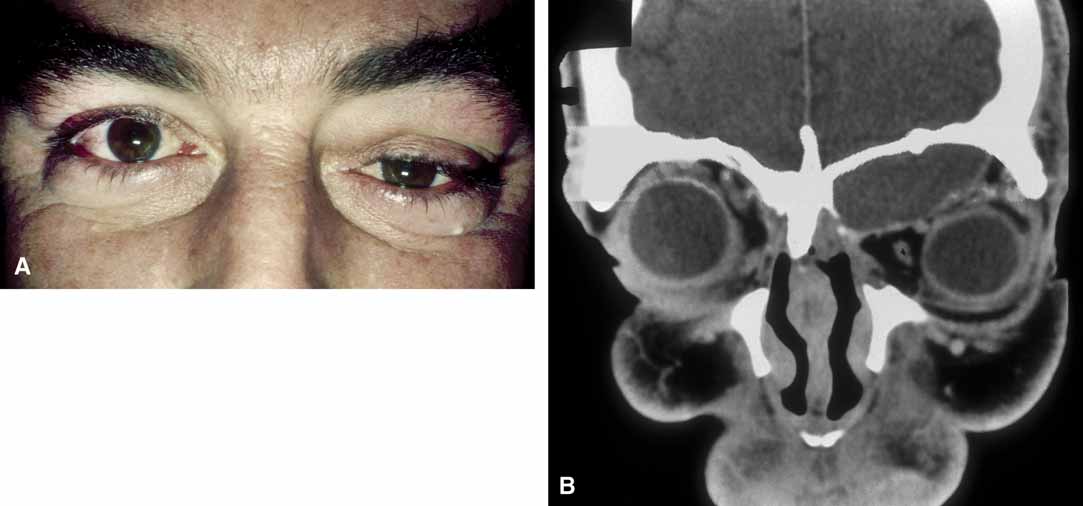

The usual cyst is a painless, smooth, ovoid-to-round, firm, rubbery mass. It may be mobile or immobile, being relatively free or firmly attached to the underlying bone (periosteum), but it is not attached to the overlying skin, distinguishing them from implantation cysts. Although contour abnormalities of the eyelid are common, there is little or no displacement of the globe with dermoid cysts located along the orbital rim. In an adult presentation, a dermoid cyst may frequently have a more posterior location.8 These posteriorly located cysts more typically present in adulthood, are more difficult to palpate, and proptosis and globe displacement are more common.

It is often cosmetic considerations that prompt the parents of an affected child to seek treatment. These cysts enlarge as the child grows and the possibility of accidental traumatic rupture is ever present. In adults, mass effect or periorbital inflammation due to leakage of cyst contents may prompt medical attention and surgical removal (Fig. 4).5,10